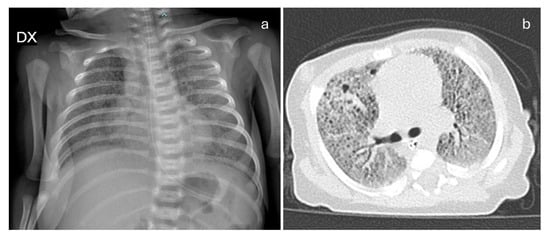

| Our case (2025) | p.Arg155Gln, p.Gly974Glu | F | Late preterm | Early onset | RDS | Yes (4 doses) | Azithromycin, hydroxychloroquine, diuretics (furosemide, spironolactone), sildenafil. Gastrostomy | Good general condition with oxygen therapy through HFNC. Impaired growth, mild motor delay. |